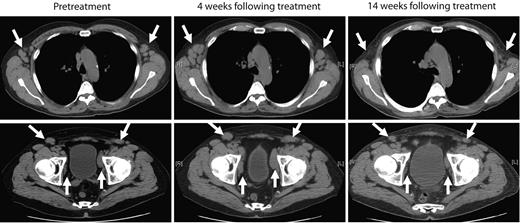

The next 4 patients (CLL-5 to -8) were treated with cyclophosphamide-conditioning chemotherapy, followed by infusion of 0.4-1.0 × 107 19-28z+ T cells/kg. Patient CLL-5 exhibited stable to progressive disease at 1 month after treatment as assessed by computed tomography scan but subsequently developed marked objective reduction of peripheral lymphadenopathy in the absence of any further therapeutic interventions, as assessed by physical examination and computed tomography scans over the subsequent 2 months (Figure 3). This marked reduction of lymphadenopathy remained stable over the subsequent 6 months, and thereafter the patient developed disease progression in the abdomen with associated ascites and worsening cytopenias, which required further chemotherapy. The patient died 15 months after T-cell therapy with progressive chemotherapy refractory disease. Patient CLL-6 exhibited progressive disease > 1 month after therapy requiring salvage chemotherapy and died of infectious complications 2 months later. Patients CLL-7 and CLL-8, both treated in the setting of rapidly progressive disease with increasing lymphadenopathy and cytopenias, exhibited stable disease with respect to lymphadenopathy over a 4- and > 2-month period of expectant management, respectively, after cyclophosphamide and T-cell infusions (data not shown).

Marked reduction of peripheral lymphadenopathy was observed after treatment with autologous 19-28z+ T cells. Representative computed tomography scan images of patient CLL-5 before treatment and from 4 weeks and 14 weeks after treatment show mild increase in axillary (top) and pelvic lymphadenopathy (bottom) at 4 weeks but regression of lymphadenopathy at 14 weeks after therapy with modified T cells.